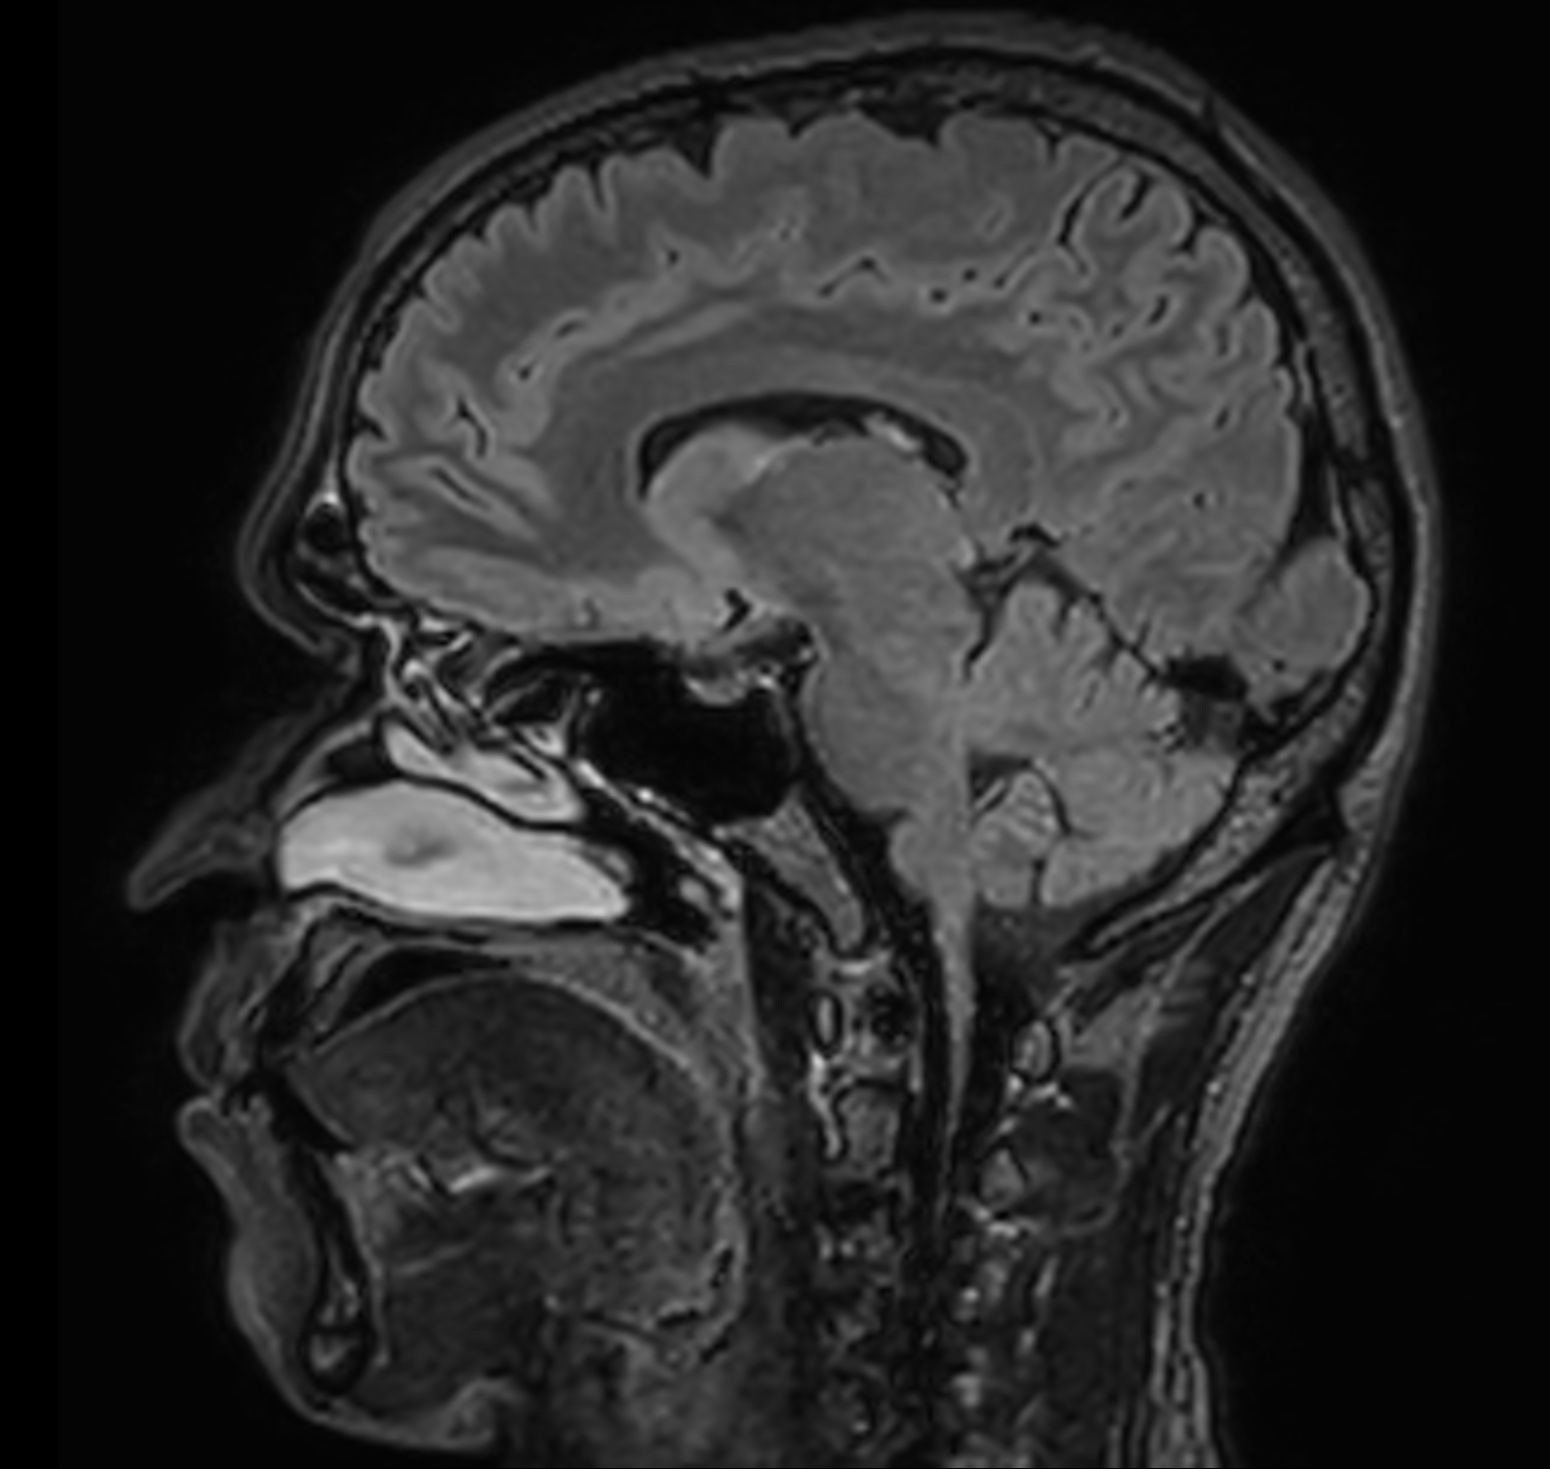

Alzheimer’s Disease Anti-Amyloid Immunotherapies (ARIA) 1.5T

Amyloid clearing medication, such as Aduhelm (Aducanumab) and Leqembi (Lecanemab) have been cleared by the FDA in 2022/2023, to slow down cognitive decline in early-stage Alzheimer’s disease. ASNR-recommendations for AD therapeutic imaging were published in 2022 for eligibility assessment as well as for monitoring for amyloid-related imaging abnormalities. This ExamCard includes ASNR-recommended consensus protocols for imaging of Alzheimer’s Disease Anti-Amyloid Immunotherapies (ARIA). (Cogswell et al., AJNR 2022,43(9)E19-E35;DOI: https://doi.org/10.3174/ajnr.A7586))